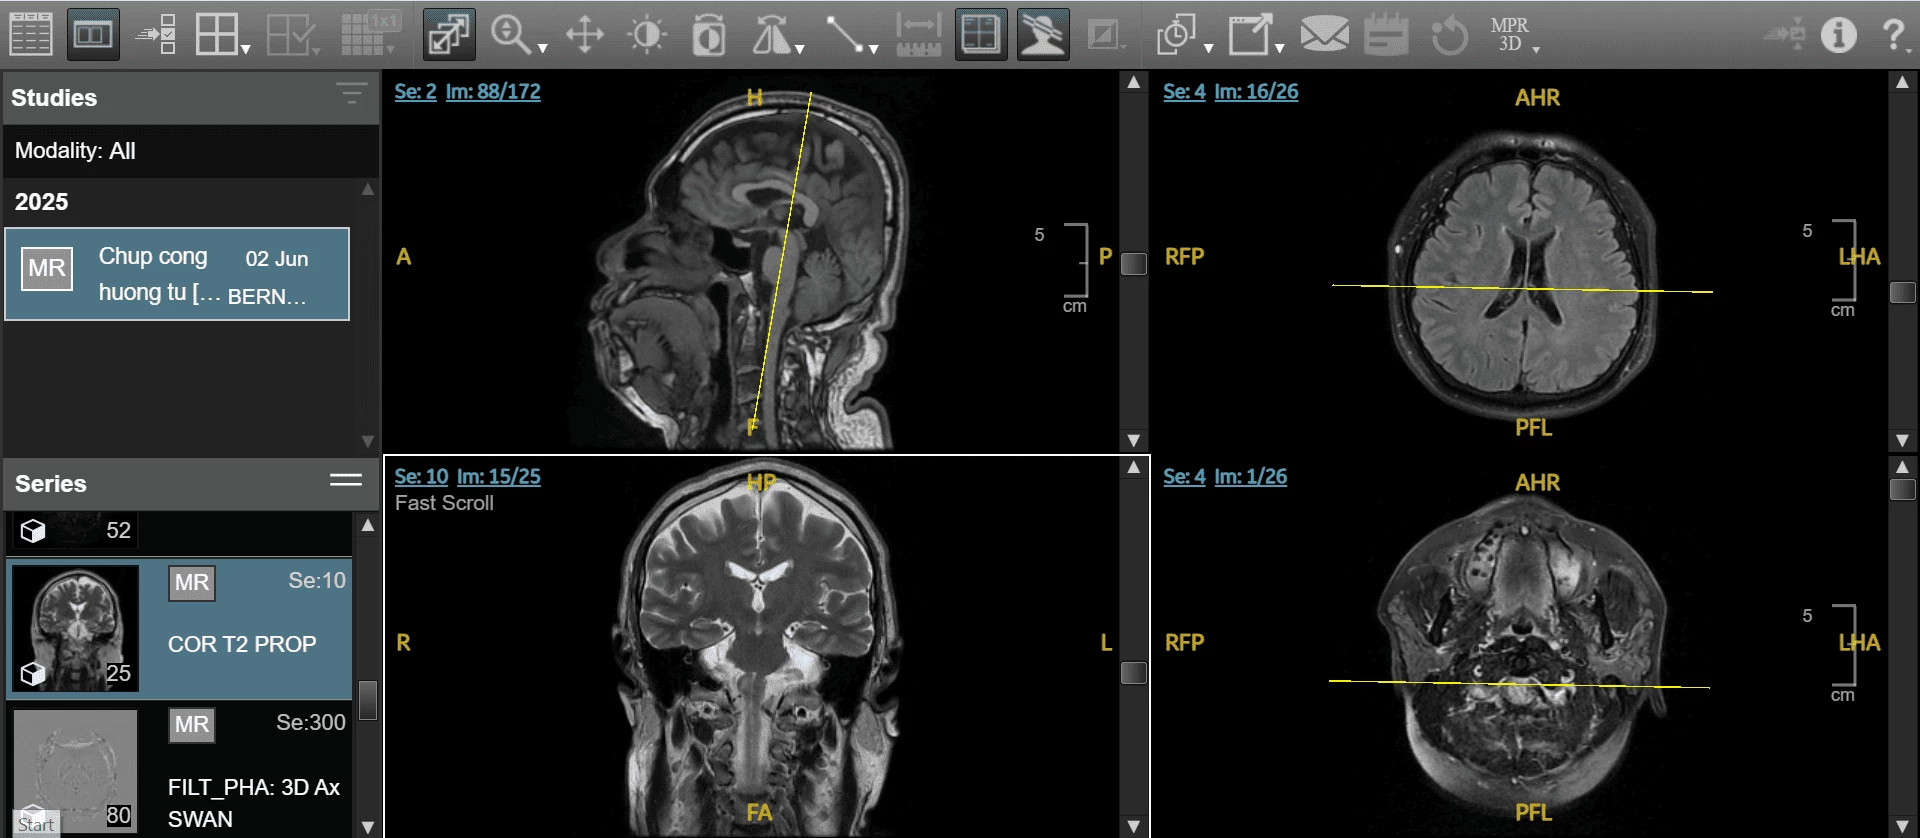

Hình ảnh MRI trên hệ thống AI PACS tại Bernard

Chụp MRI não bộ, chụp MRI nhũ, chụp MRI toàn thân

MRI với công nghệ dựng hình chuyên sâu AI PACs giúp các bác sĩ Bernard khảo sát mạch máu não, dựng hình 3D mạch máu não và đánh giá tưới máu não, từ đó truy tìm ra các yếu tố nguy cơ thầm lặng gây đột quỵ

Trong lĩnh vực ung thư, MRI 1.5 Tesla có thể khảo sát các bộ phận của cơ thể trong thời gian nhanh nhất nhằm phát hiện những tổn thương, sang thương, khối u rất nhỏ như u não, ung thư phổi, ung thư vú, ung thư hạch (lympho), ung thư vùng sâu, hố chậu,... và thay đổi bất thường khác trong các mô mà những phương pháp chẩn đoán khác có thể bỏ qua.